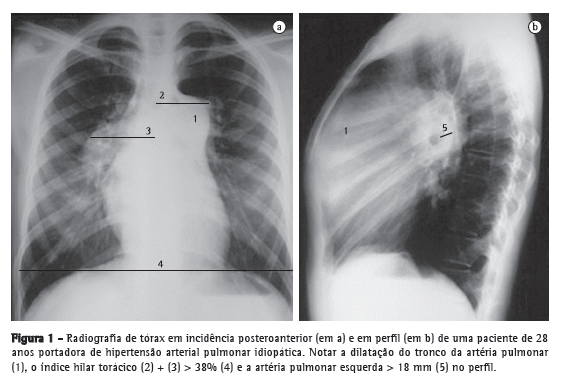

Pacientes com diagnóstico confirmado de HP apresentam alterações na radiografia de tórax em mais de 85% dos casos.(4) As principais alterações encontradas são aumento do calibre das artérias pulmonares no nível dos hilos, em 78% dos casos (Figura 1); afilamento periférico dos vasos, em 62%; e periferia pulmonar hiperlucente, em 9% (Figura 2).

O aumento do calibre das artérias pulmonares no nível dos hilos pode ser avaliado pela medida do diâmetro das artérias interlobares. O limite máximo do diâmetro transversal da artéria interlobar direita, medido de sua face lateral até a coluna de ar do brônquio intermediário, é de 16 mm em homens e de 15 mm em mulheres.(5) Devido à dificuldade de se realizar a avaliação da artéria pulmonar esquerda na incidência posteroanterior, deve-se avaliar o vaso na radiografia em perfil, partindo da transparência circular criada pelo brônquio do lobo superior esquerdo (que é visto telescopado), até a margem posterior do vaso que cavalga o brônquio; o limite máximo do normal é de 18 mm (Figura 1). O índice hilar torácico (soma da medida separada dos hilos pulmonares em relação ao diâmetro torácico total) maior do que 38% é classicamente descrito, e está presente em aproximadamente 75% dos pacientes com HP (Figura 1).(6) Raramente pode ser evidenciada a calcificação vascular, localizada geralmente no tronco da artéria pulmonar (TAP) ou em seus ramos hilares. Essa alteração é mais frequentemente relacionada a cardiopatias congênitas e embolia central crônica.